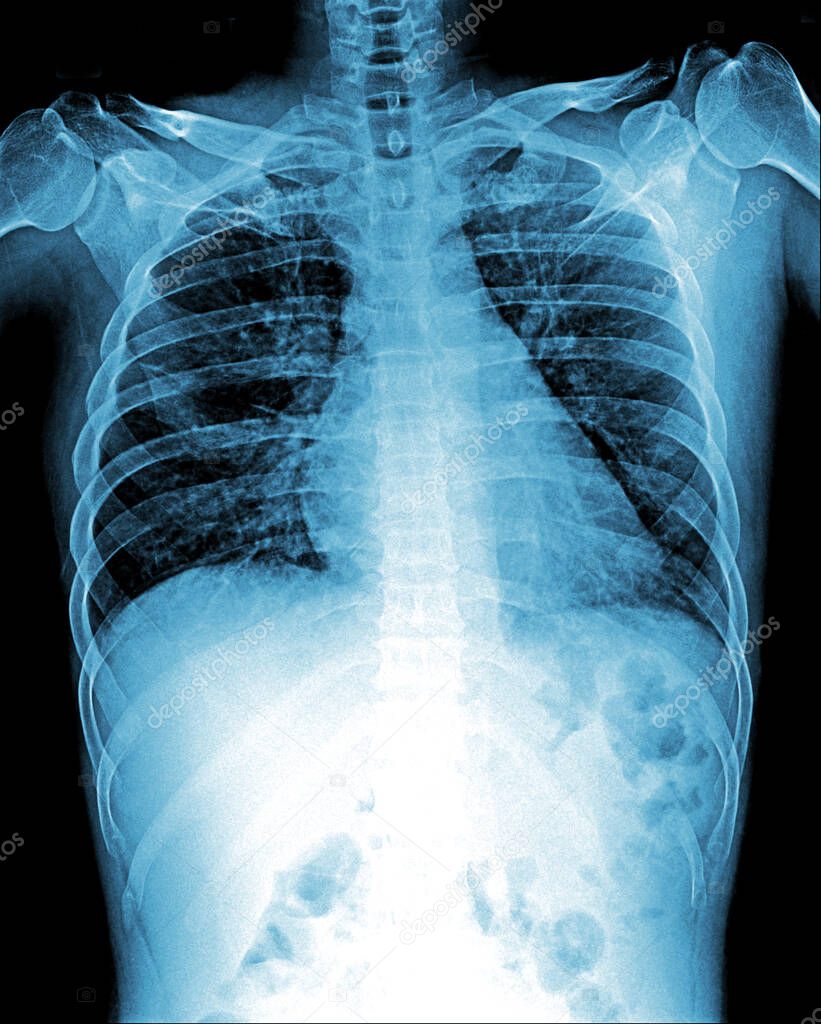

Imagen De Rayos X De Cuerpo Entero Para Diagnóstico Médico Fotografía

www.alamy.es

www.alamy.es